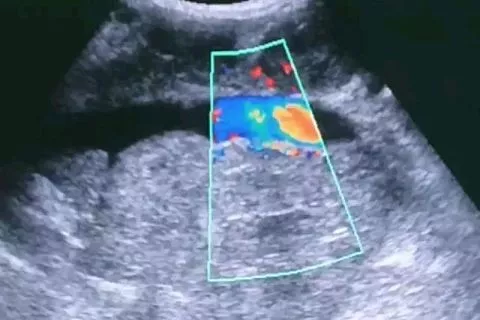

В результате обследования была обнаружена циркулярно охватывающая, но не сдавливающая брюшной отдел аорты и нижнюю полую вену, забрюшинная опухоль размером 15 на 9 сантиметров. Кроме того, выявлены множественные патологически измененные забрюшинные лимфоузлы.

Предположительно, у пациента лимфома. Он направлен на консультацию онколога, сообщили в пресс-службе ККБ №2.